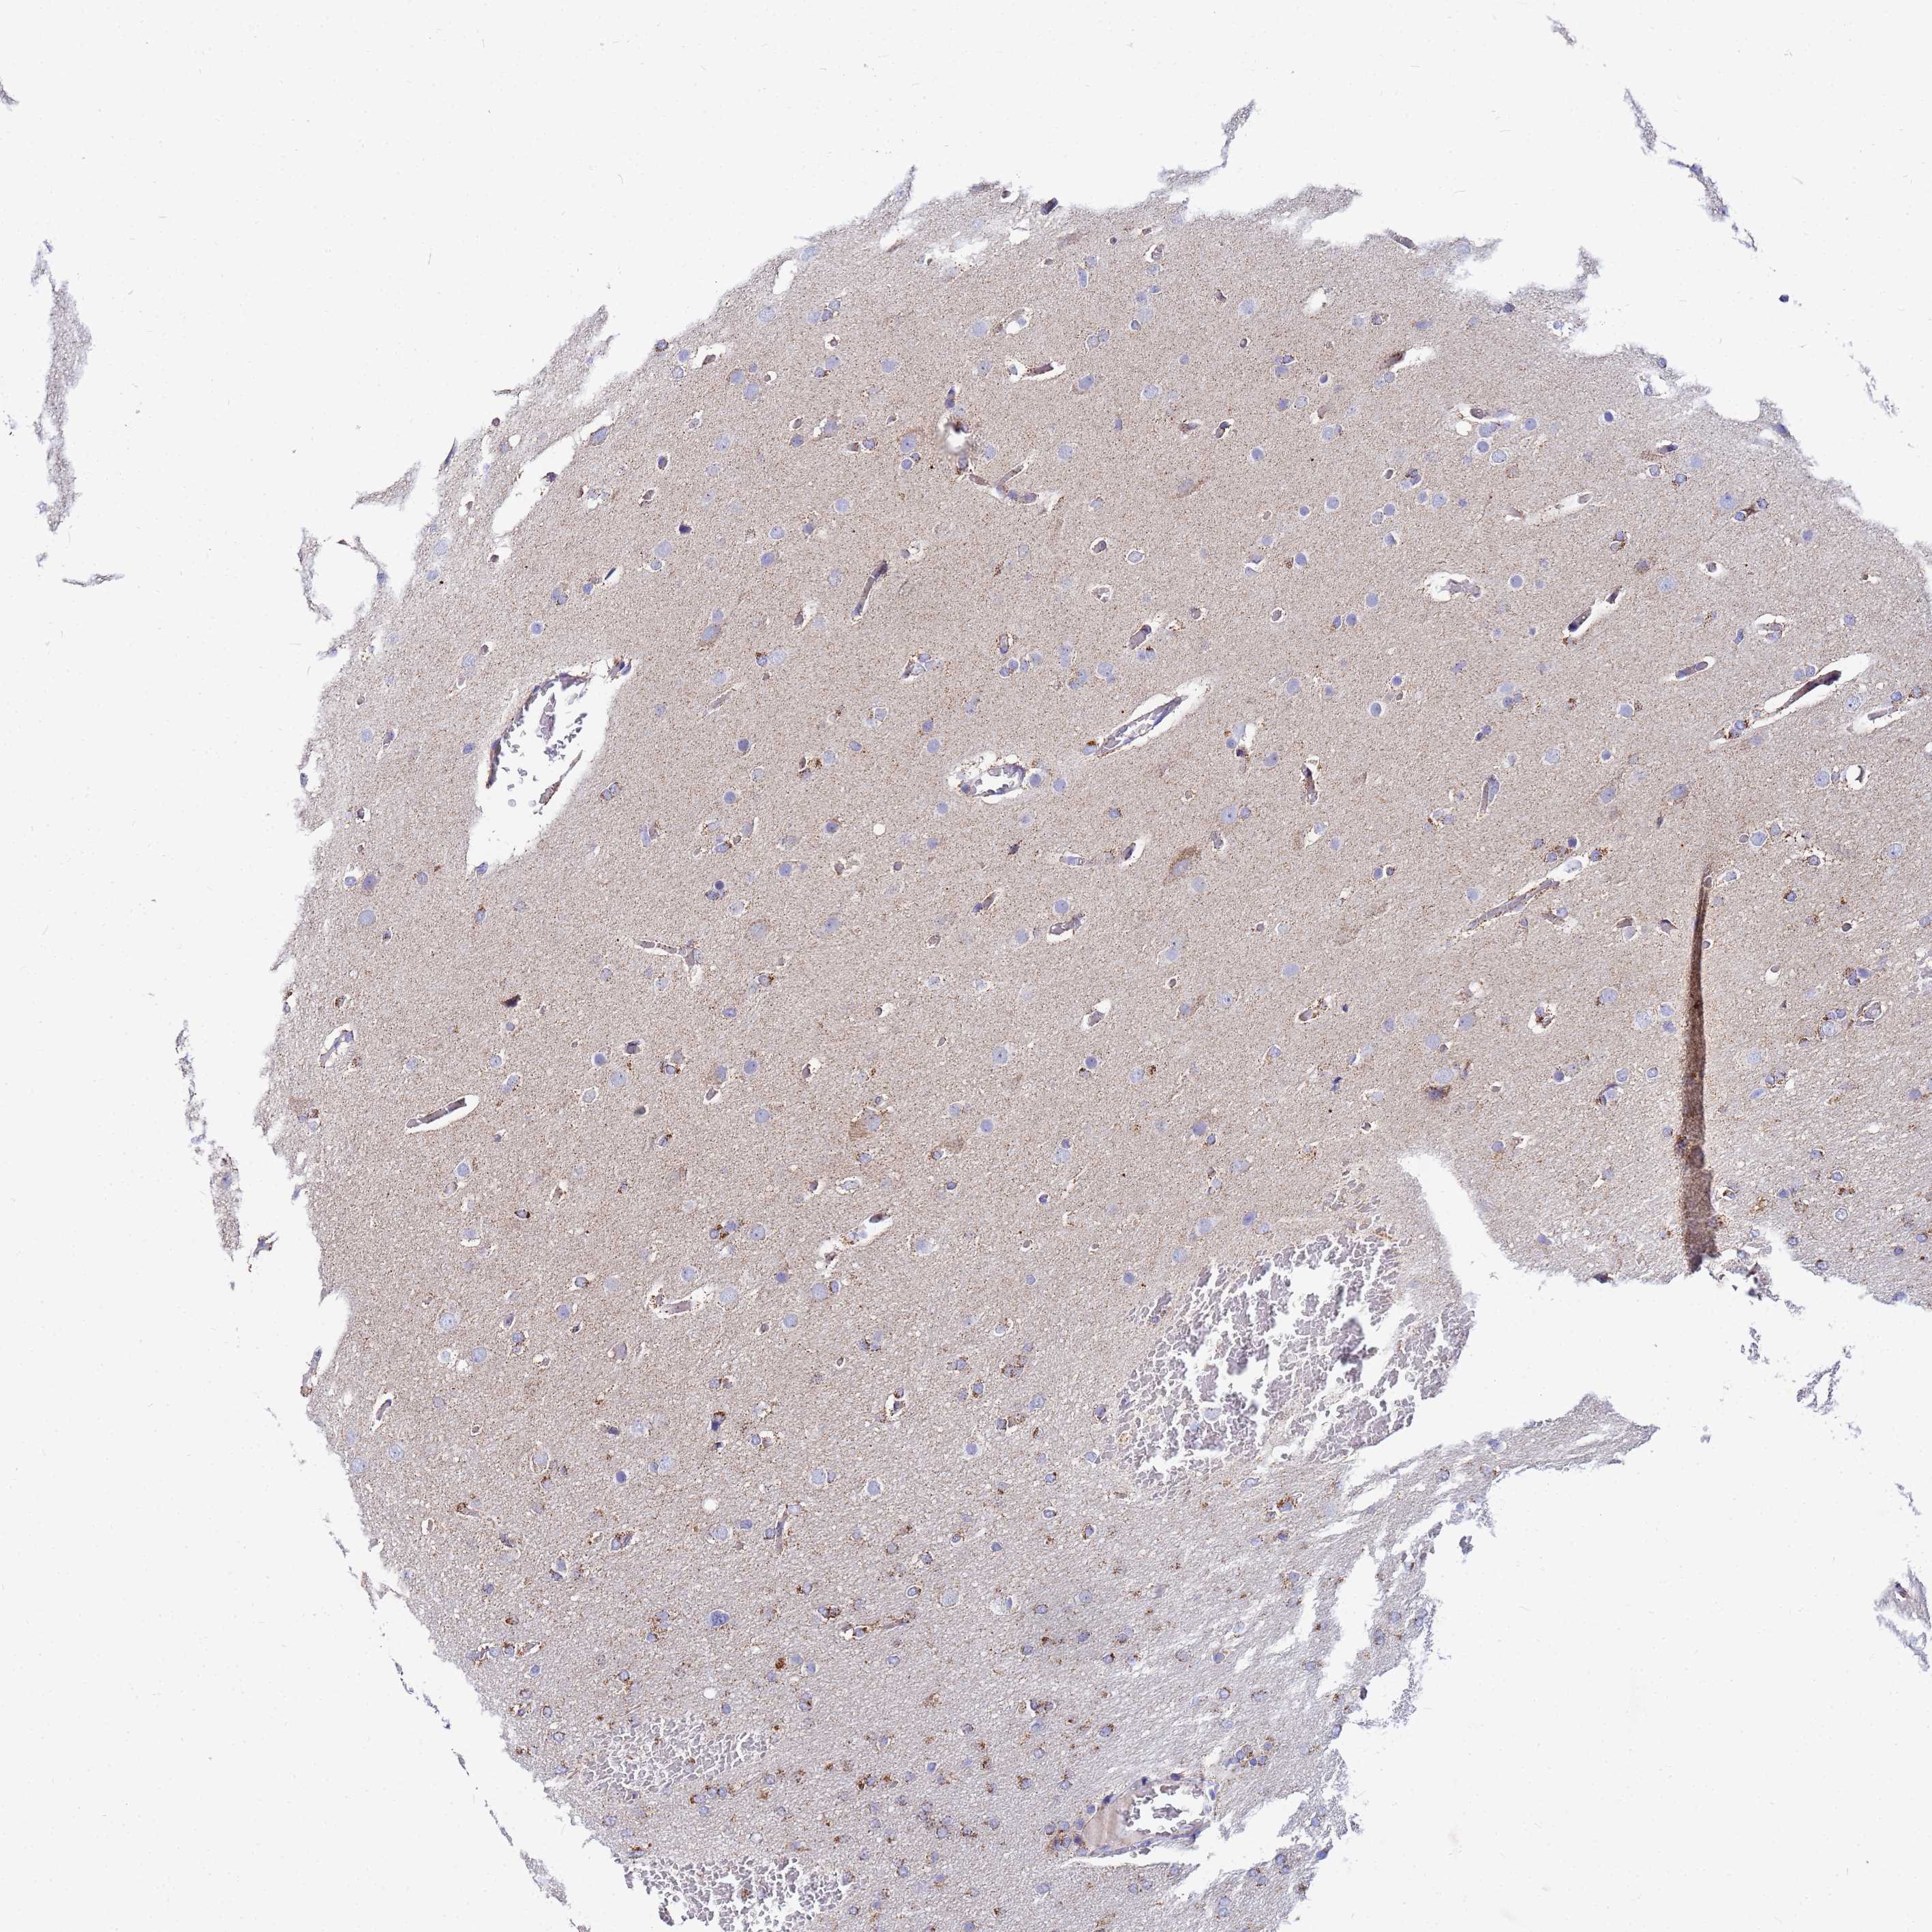

GLIOMA - Protein expressioni

A mouse-over function shows sample information and annotation data. Click on an image to view it in a full screen mode. Samples can be filtered based on level of antibody staining by selecting one or several of the following categories: high, medium, low and not detected. The assay and annotation is described here.

Note that samples used for immunohistochemistry by the Human Protein Atlas do not correspond to samples in the TCGA dataset.

Antibody stainingi

Antibody staining in the annotated cell types in the current human tissue is reported as not detected, low, medium, or high, based on conventional immunohistochemistry profiling in selected tissues. This score is based on the combination of the staining intensity and fraction of stained cells.

Each image is clickable and will lead to virtual microscopy that enables deeper exploration of all samples and also displays staining intensity scores, fraction scores and subcellular localization as well as patient and tissue information for each sample.

Antibody HPA042145

Antibody HPA044987

Antibody CAB045971

Antibody CAB045972

Staining

High

Medium

Low

Not detected

Intensity

Strong

Moderate

Weak

Negative

Quantity

>75%

75%-25%

<25%

None

Location

Nuclear

Cytoplasmic/membranous

Cytoplasmic/membranous,nuclear

Glioma, malignant, Low grade

Glioma, malignant, High grade